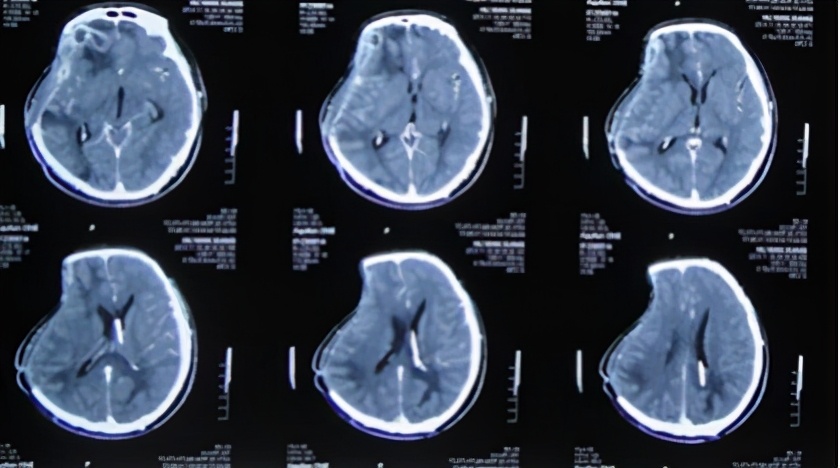

2013年10月27日即入院术后第26天(开颅术后第40天),但间断叙述头痛并夜间躁动不安,当晚复查头颅CT:脑膨出、脑肿胀进一步改善(图-13)。

图-13:2013年10月27日头CT

2013年10月29日即入院术后第28天(开颅术后第42天),行头CT增强扫描发现右侧大脑半球多发脑脓肿(图-14),遂给予抗感染治疗。

图-14:2013年10月29日头CT增强扫描

2013年11月19日即抗感染21天后即入院术后第49天(开颅术后第65天),再次复查头CT:右侧大脑半球多发脑脓肿及脑膨出均较前减轻(图-15),继续给予抗感染治疗。

图-15:2013年11月19日头CT

2013年11月21日即抗感染23天后即入院术后第51天(开颅术后第67天),给予试夹闭引流管观察骨窗情况。但在夹毕引流管次日患者出现右侧骨窗膨隆伴嗜睡,复查头CT:脑室系统扩张明显(图-16),再次给予开放脑脊液引流管。

图-16:2013年11月22日头CT

2013年12月17日即继续脑脊液引流25天后即入院术后第77天(开颅术后第93天),进行了侧脑室腹腔分流术,分流术后第1天2013年12月18日术后情况稳定(图-17)。

图-17:2013年12月18日

术后患者恢复良好,但仍间断头痛发作,在2013年12月25日即分流术后第8天(开颅术后第101天),复查头CT:脑室无异常(图-18)。

图-18:2013年12月25日头CT